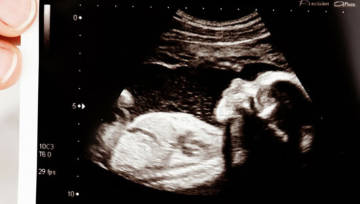

Badanie USG ginekologiczne przeprowadzane jest w ramach przygotowywania pacjentki do zajścia w ciążę i przy monitorowaniu jej przebiegu. W pierwszym trymestrze ginekolog-położnik najczęściej przeprowadza USG dopochwowe, ale w miarę rozwoju ciąży decyduje się na USG przez powłoki brzuszne w celu uzyskania prawidłowego obrazu płodu.

W trakcie badania USG transwaginalnego kobieta pozostaje w pozycji leżącej, z podciągniętym w górę jednym lub dwoma kolanami. Lekarz ginekolog wprowadza specjalną sondę ultrasonograficzną do pochwy pacjentki i precyzyjnie ocenia obraz narządu rozrodczego widoczny na monitorze. USG dopochwowe cechuje się wysoką dokładnością – wyższą niż w przypadku wykonania USG przez powłoki brzuszne. Lekarz w czasie badania może dokonać oceny kształtu i wielkości narządów rodnych kobiety i okolicznych struktur.

Wartość takiego badania jest więc wysoka. Ginekolog może stwierdzić ewentualną obecność guzów, zmian nowotworowych, stanów patologicznych lub ocenić, czy nie dochodzi do żadnych niepokojących sytuacji zdrowotnych. Badanie wykorzystywane jest do kontroli rozwoju płodu podczas ciąży – zarówno w pierwszych jej tygodniach, jak i później. Oba te badania są przeprowadzane jednak w innym trybie.